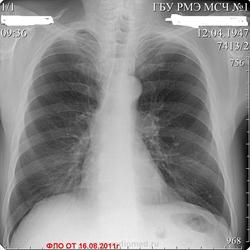

Пациент 65 лет, проходил проверочное флюорографическое исследование лёгких. Жалоб не предъявляет.В качестве дообследования назначена R-графия лёгких в 2-х проекциях.О чём можно думать?

По мне - центральный рак слева, ателектаз четверки, вздута пятерка. По сегментам могу и ошибаться, но идея такая.

+1 и кажется восьмерка заинтересована.

Я за рак слева.

но не надо торопиься с выводами КТ специалистов. Если рак, то хотелось знать направление роста, экзофитный ? эндофитный? По рентгенограммам можно высказаться о наличии патологического процесса в корне левого легкого. Это прежде всего дополнительная тень в области головки, реакция междолевой щели и межсегментарной перегородки. О гиповентиляции можно судить по сгущению сосудистого рисунка на боковой рентгенограмме (см. рисунок). Наличие обызвествленного первичного комплекса слева, не позволяет исключить реактивацию туберкулеза во внутригрудых имфатических узлах со всеми вытекающими последствиями, отраженными на рентгенограммах. Бронхоскопия необходима в 100%. Вы несколько поторопились коллега Алмо представить данные КТ. Хотелость бы услышать мнения многих врачей. Если будет окончательная морфологическая верификация, напишите.

Я б написала спайки и расширение корня. Такое может быть после перенесенной пневмонии.

Томография на левом боку многое разъяснит. Аталектаз 3 сегмента явный в купе с реакцией корня левого лёгкого.